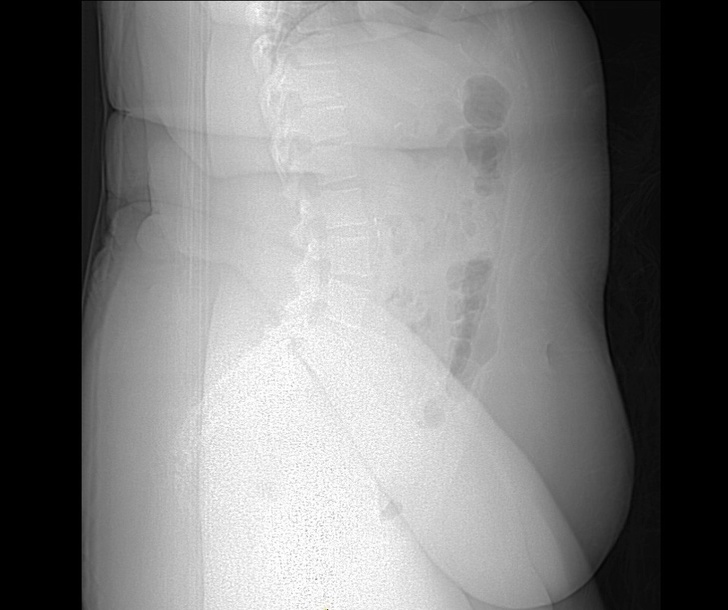

8. Рентгенівський знімок людини з ожирінням. Надмірна кількість жирової тканини заважає видимості кісток